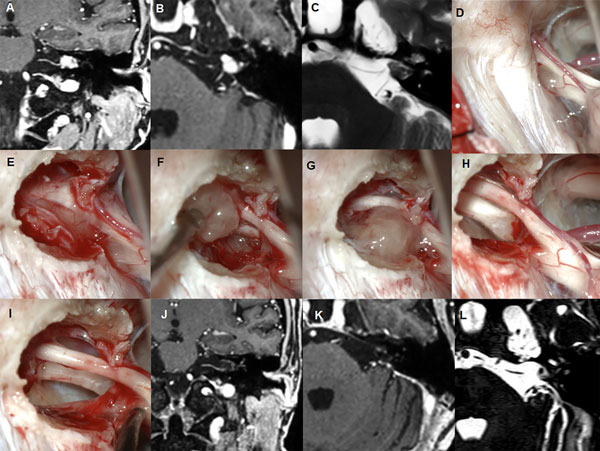

Figura 2: Paciente masculino de 59 años, operado de SV T1 izquierdo. A-C: RM preoperatoria. D-I: hallazgos intraoperatorios. J-L: RM postoperatoria.